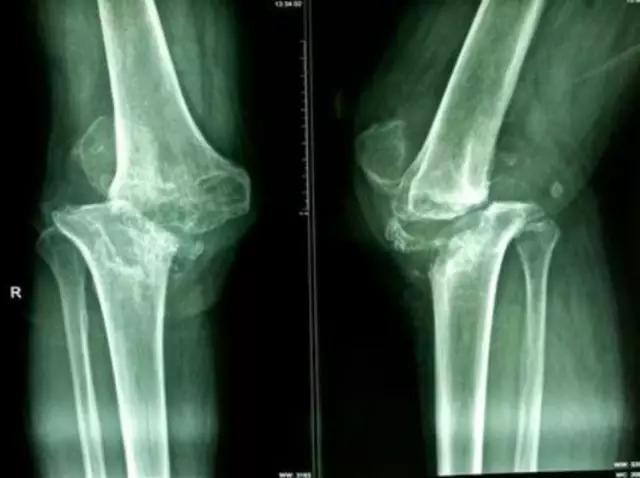

病例:游XX,男,67岁,右膝肿胀活动困难伴进行性畸形6年。疼痛不重!下图为2010年照片,DR和MR显示胫骨内侧平台骨缺损,无其他病变,很难确诊。

利用疾病发展——

下图为2014年DR,显示关节破坏严重,但疼痛不重,符合神经性关节炎的疾病特点:关节破坏极度严重,临床症状轻微!